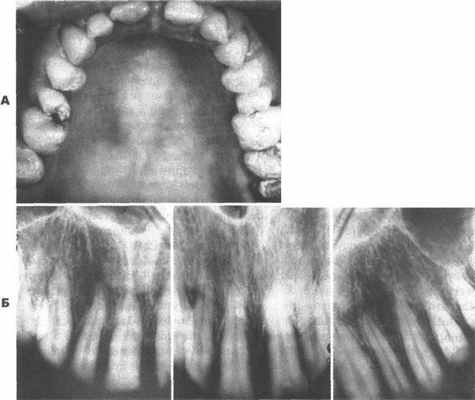

Поражение зубов ограничивается дефектом эмали. На рентгенограмме конфигурация пульпарной камеры и корневых каналов выглядит нормальной. Различия во внешнем виде и структуре эмали зависят от периода развития, на котором находилась эмаль в период формирования дефекта. При гипопластическом типе аномалии эмалевая матрица не полностью сформирована, а т. к. постепенно происходит минерализация эмалевой матрицы, эмаль становится твердой, но ее количество уменьшено и она имеет грубую пятнистую поверхность (рис. 7.27).

Рис. 7.27. Как молочные, так и постоянные Рис. 7.28. Гипокальцифицированный тип

зубы имеют наследственную аномалию – несовершенного амелогенеза. Молочные

несовершенный амелогенез. Эмаль пятнистая, зубы одинаково поражены. Поверхность

но твердая. эмали мягкая.

При гипокальцифицированном типе эмалевая матрица сформирована полностью, но недостаточно минерализована, поэтому эмаль становится мягкой (рис. 7.28). В обоих, наиболее часто встречающихся, типах данной аномалии эмаль имеет пятнистый вид из-за грубой поверхности и увеличенной проницаемости.

Рис. 7.29. А - несовершенный амелогенез. Постоянные зубы покрыты тонким слоем пигментированной эмали; Б - на рентгенограмме существенных изменений в морфологии корней зубов не наблюдается. Коронки покрыты тонким слоем эмали.

При другом типе несовершенного амелогенеза эмаль тонкая, гладкая, имеет коричневато-желтый цвет. Такая эмаль мало подвержена истиранию и кариесу (рис. 7.29 и 7.30).